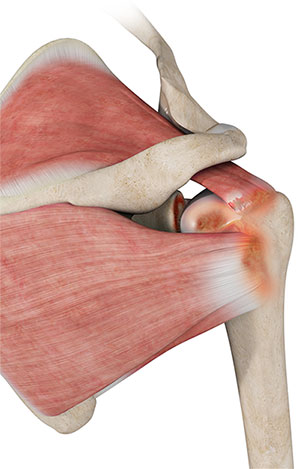

Rotator Cuff Tear

A rotator cuff tear is an injury where one or more of the tendons in the rotator cuff (the group of muscles and tendons that stabilize the shoulder and enable arm movement) become partially or completely torn.

Rotator Cuff Arthropathy

The rotator cuff consists of 4 muscles that stabilize the ball and socket joint of the shoulder during movement.